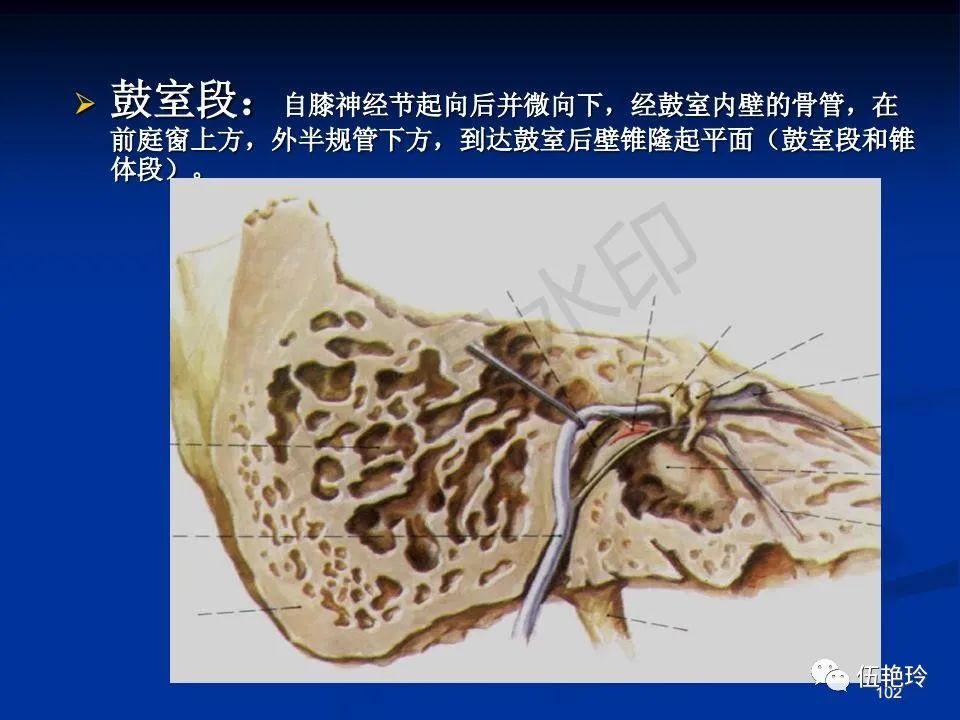

耳与面神经的解剖